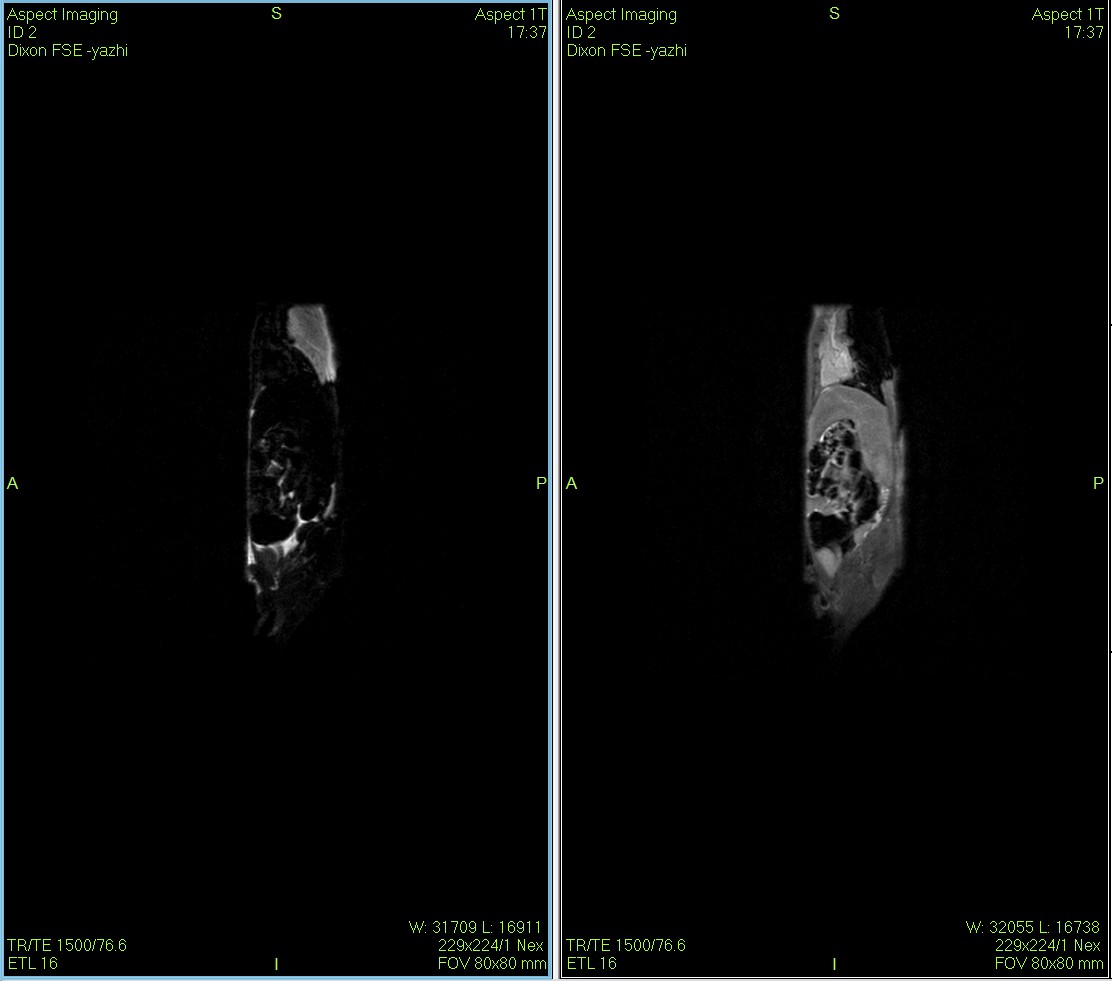

Dixon序列用于大鼠、小鼠水脂分离磁共振成像-脂肪抑制技术

传统的体成分分析只能告诉我们“脂肪多了多少克”,而QMR的成像技术能告诉我们“脂肪长在了哪里”。本案例通过高分辨率的核磁成像,直观展示了高脂饮食小鼠腹部内脏脂肪 (Visceral Fat) 的显著堆积,实现了从“定量分析”到“形态学定位”的维度跨越。

低场核磁共振技术,已被广泛应用于小动物(大、小鼠)实验模型中,用于监测体内脂肪分布及沉积情况。这不仅有助于揭示人类肥胖代谢性疾病的病因,还为肥胖治疗药物的评价提供了重要依据。通过低场核磁共振技术结果表征,科研工作者能够直观地观察到小鼠体内脂肪的变化,从而更深入地理解肥胖症的发病机制。

Dixon脂肪抑制技术是由Dixon 提出,其基本原理是利用水、脂肪的化学位移差异,使用不同的回波时问,分别采集水和脂肪质子的in Phase 和 opposed -phase两种回波信号。